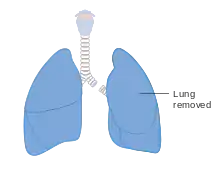

Diagram showing the parts removed in a pneumonectomy